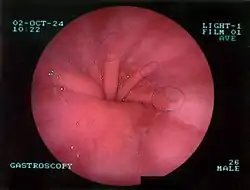

Upper GI endoscopy depicting hiatal hernia